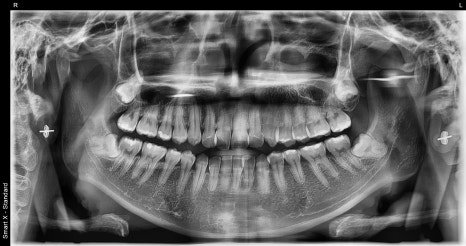

A woman in her 20s, a case seeking naturalness

This patient visited the clinic wanting

to improve her front teeth in a way that would look naturally beautiful.

Rather than excessively white teeth,

she wanted results that suited her own image,

and based on that, a treatment plan was established using the Obzero Pure Line for the six front teeth.